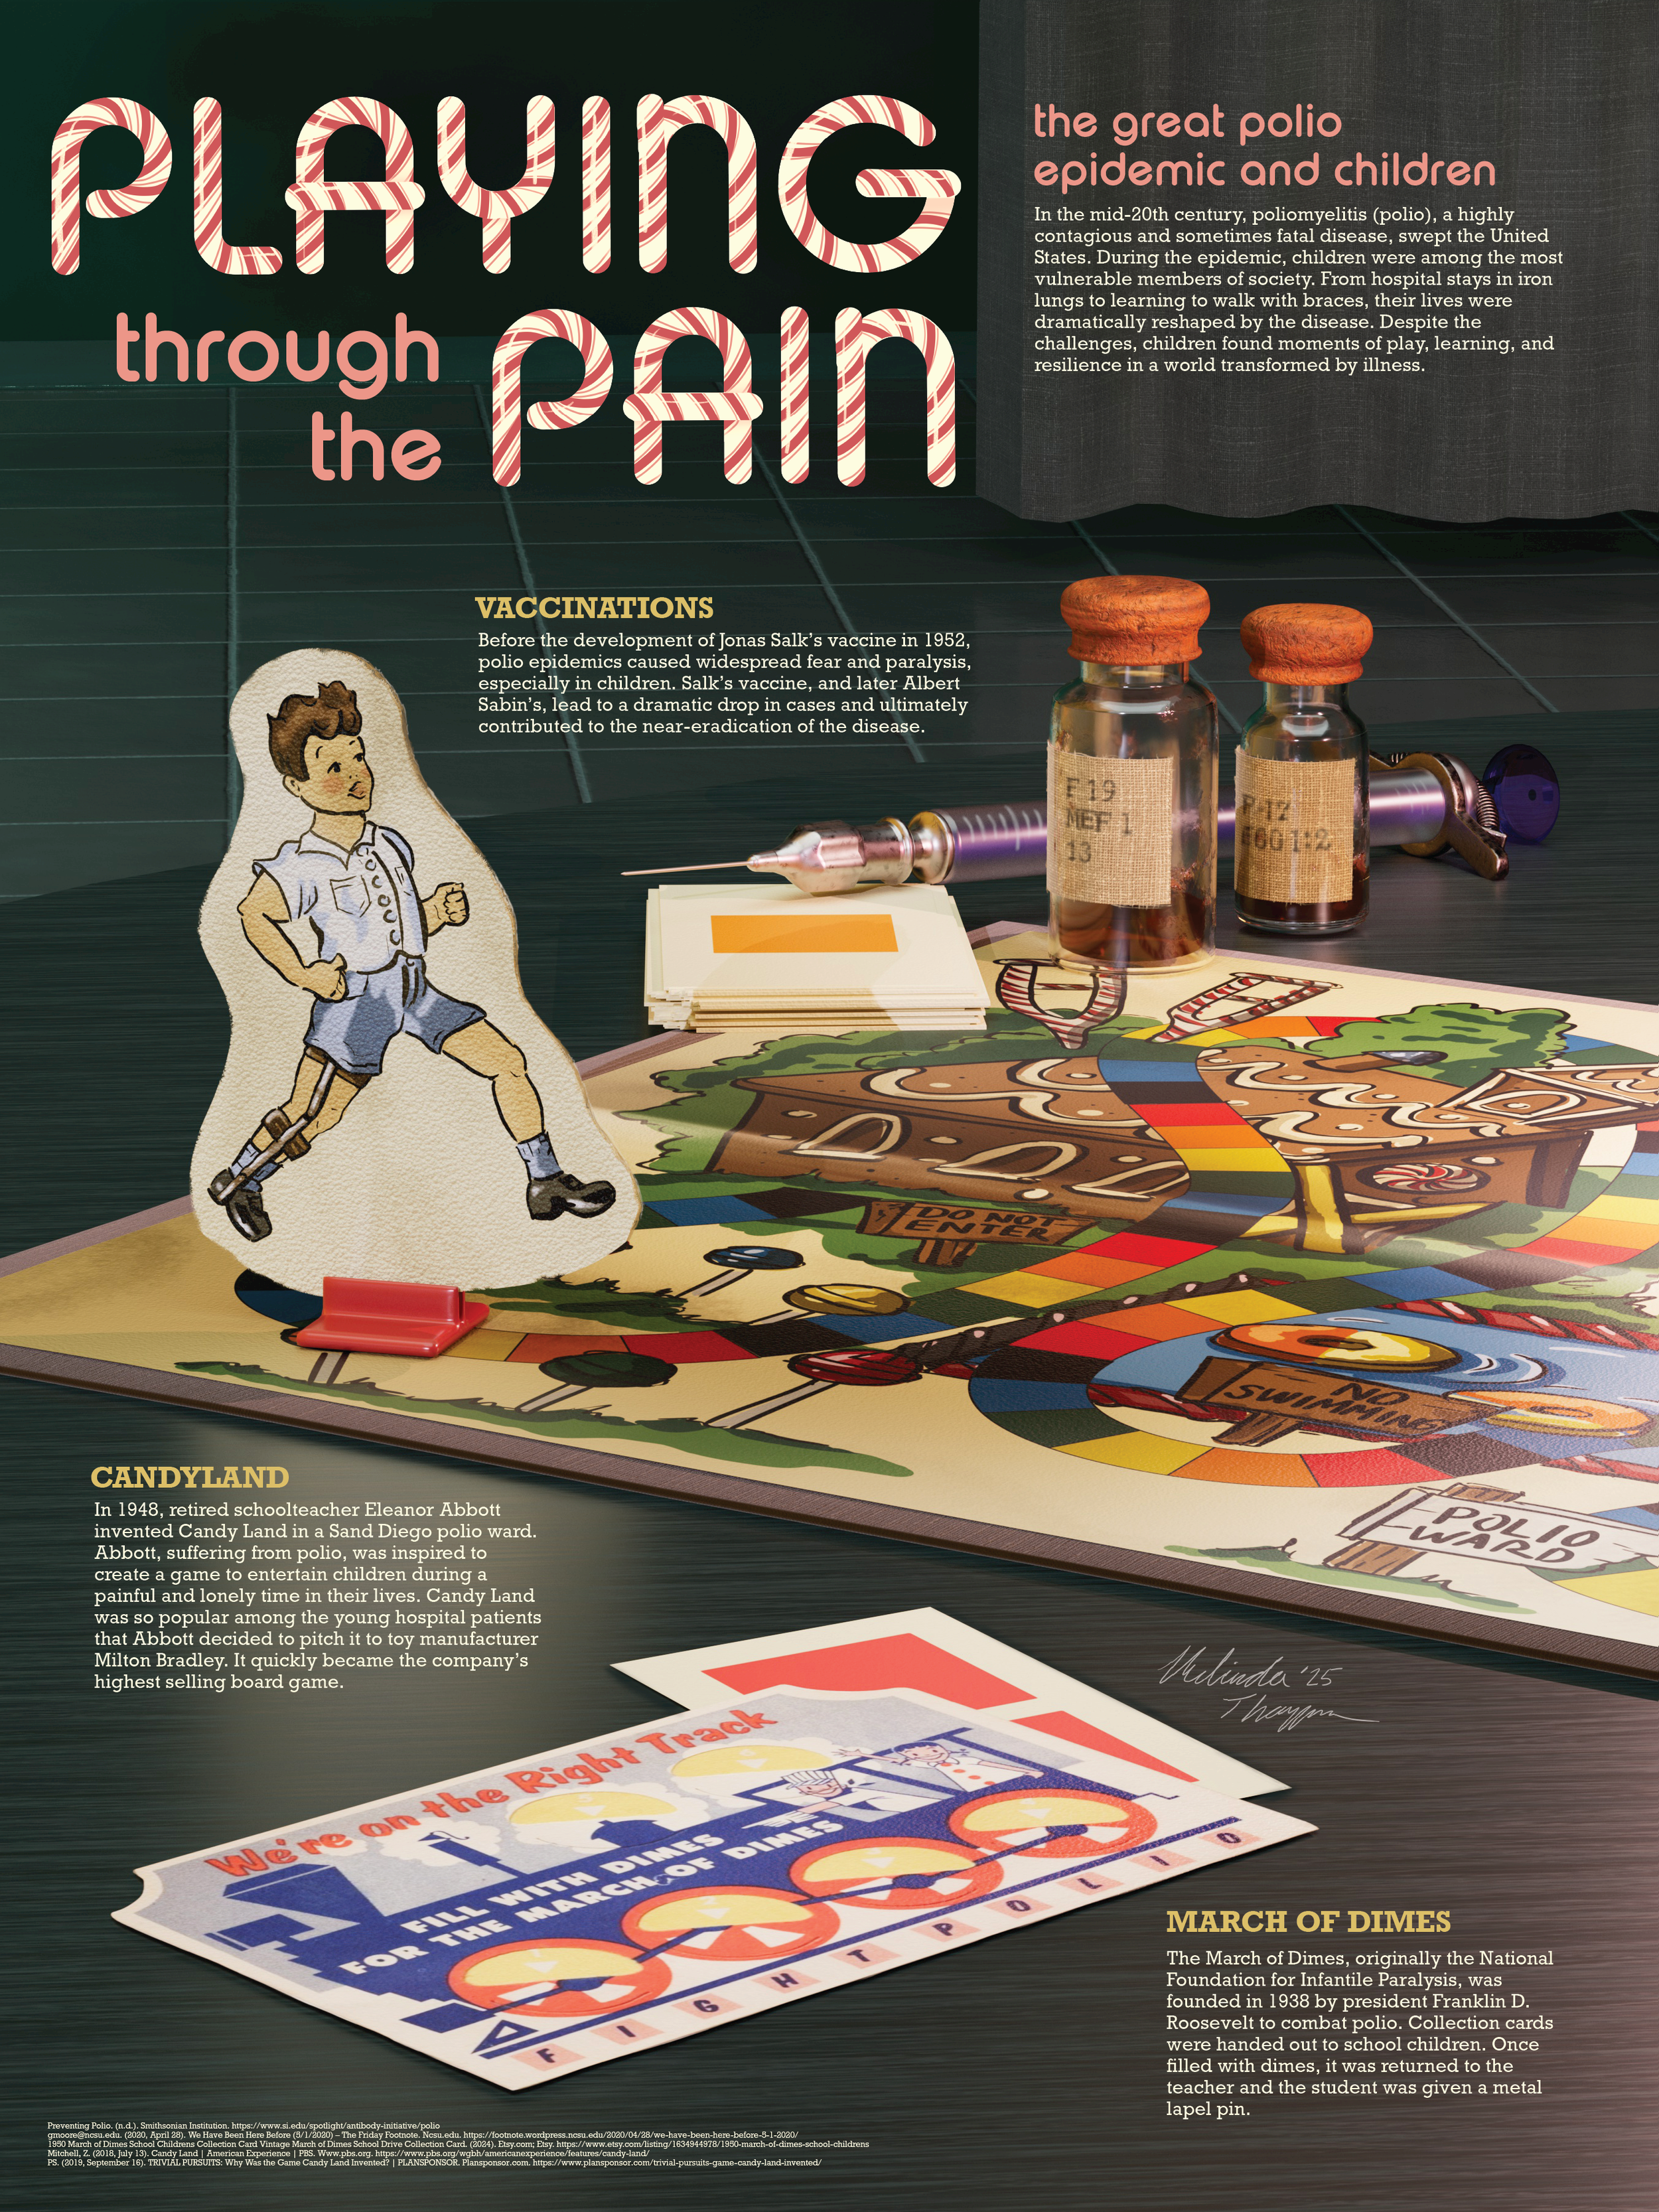

Historical Museum Poster: Playing through the Pain